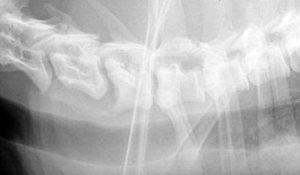

photo 3

Figure 3 : Sur ce doberman atteint de wobbler, on note la malformation de C7 ainsi que la sténose canalaire en regard de C6-C7

Des moyens d’imagerie sont nécessaires pour poser le diagnostic de syndrome Wobbler. La radiographie présente un intérêt limité dans la mesure où le peu de modifications qu’elle peut mettre en évidence (forme de vertèbre anormale, rétrécissement d’un espace intervertébral ou sténose du canal vertébral) se retrouvent chez 20 à 25 % des chiens sains (Figure 3).